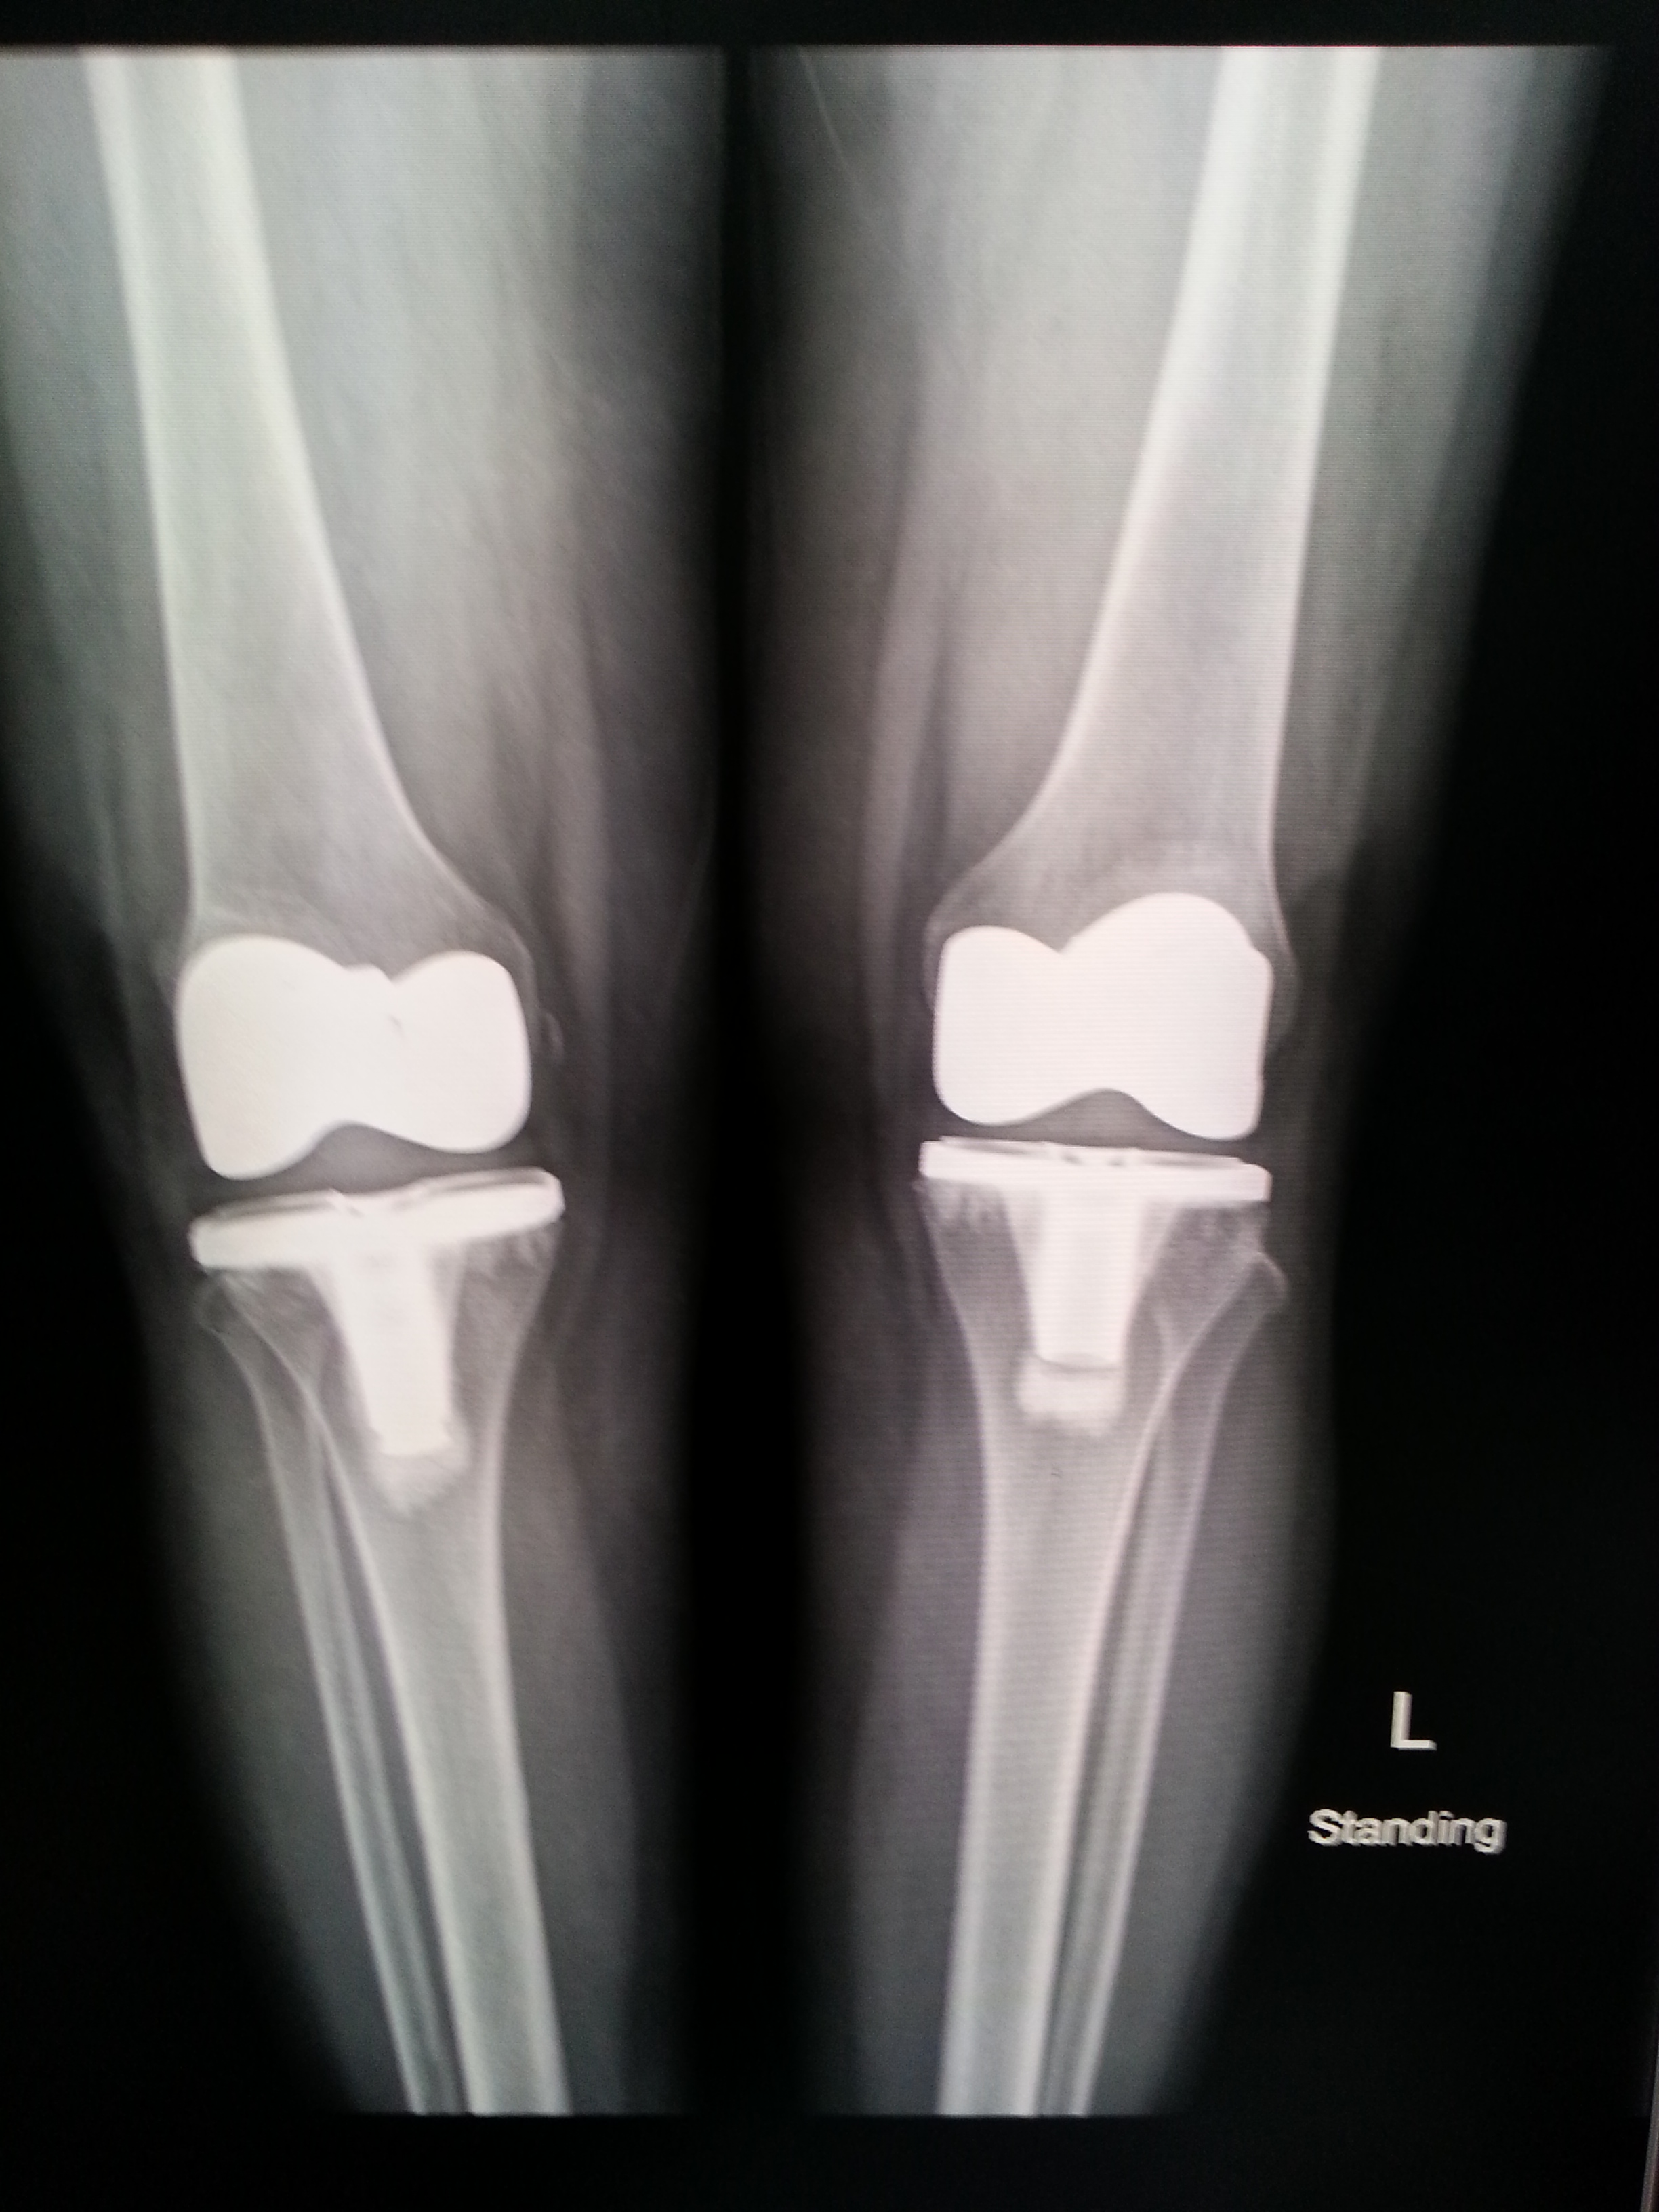

พอไปถึงก็จับเอ็กซ์เรย์ เพื่อรอแผ่นฟิล์มให้คุณหมอตรวจดู อาการเข่าเสื่อมของแม่ ก็พบว่าข้างขวาเสื่อมแน่ ๆ ส่วนข้างซ้าย ก็มีอาการเสื่อมแต่น้อยกว่า ตัดสินใจผ่าทีเดียวทั้งสองข้าง การผ่าตัดมีทั้งเปลี่ยนเฉพาะบางส่วน และเปลี่ยนเต็มข้อ สำหรับของแม่จัดเต็มข้อทั้งสองข้างเลยทีเดียว

ฟิล์มเอ็กซเรย์ก่อน (ภาพซ้าย) และหลัง (ภาพขวา) ของการผ่าตัดข้อเข่าเทียม ส่วนก้อนสีขาว ๆ ของภาพทางขวามือ คือข้อเข่าเทียมที่ใส่เข้าไป

วันนี้คุณหมอนัดตรวจและมี X-Ray สภาพข้อเข่า เช็คการพับงอ ทุกอย่างผ่านไปด้วยดี (ต้องยกผลงานให้คุณหมอเลย เก่งมาก ๆ )

คนไข้รอคิวกันเยอะแยะมากมายเหมือนเดิม นั่งคุยถ่ายทอดประสบการณ์แลกเปลี่ยน ทั้งคนที่มาตรวจกำลังตัดสินใจ คนที่ผ่าแล้ว คนที่อยู่ระหว่างรักษาตัว ค่าใช้จ่ายในการตรวจและ X-Ray วันนี้ 1,420.-